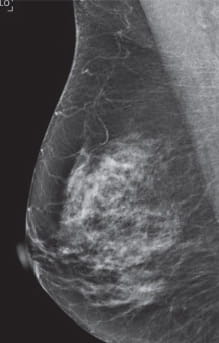

Radiologists classify breast density using a four-level density scale, as determined by a mammogram:

- Category A: Almost entirely fatty

- Category B: Scattered areas of dense breast tissue

- Category C: Heterogeneously dense

- Category D: Extremely dense

Having dense breast tissue may increase your chance of getting breast cancer. Dense breasts also make it more difficult for doctors to spot cancer on mammograms. Dense tissue appears white on a mammogram; lumps, both benign and cancerous, also appear white. So mammograms can be less accurate in women with dense breast tissue.